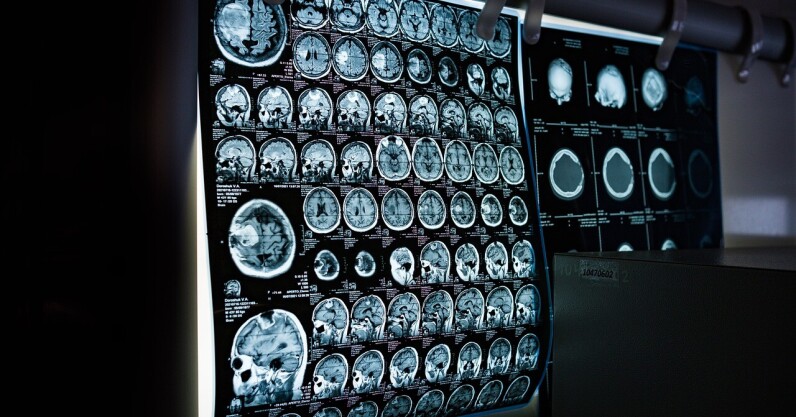

AI could be nearly twice as accurate as biopsies at assessing the aggressiveness of some rare types of cancer, a new study suggests. According to researchers this could save the lives of thousands of patients. A research team from the Royal Marsden NHS Foundation Trust and the Institute for Cancer Research (ICR) focused on retroperitoneal sarcoma — a form of soft tissue sarcoma that develops in the back of the abdomen. “There is an urgent need to improve the diagnosis and treatment of patients with retroperitoneal sarcoma, who currently have poor outcomes,” said Dr Amani Arthur, first author of the…